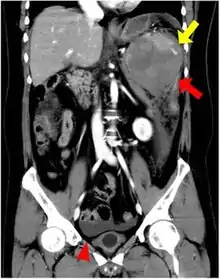

| CT scan of an accessory spleen (circular object in center of image) between the spleen and left kidney. | |